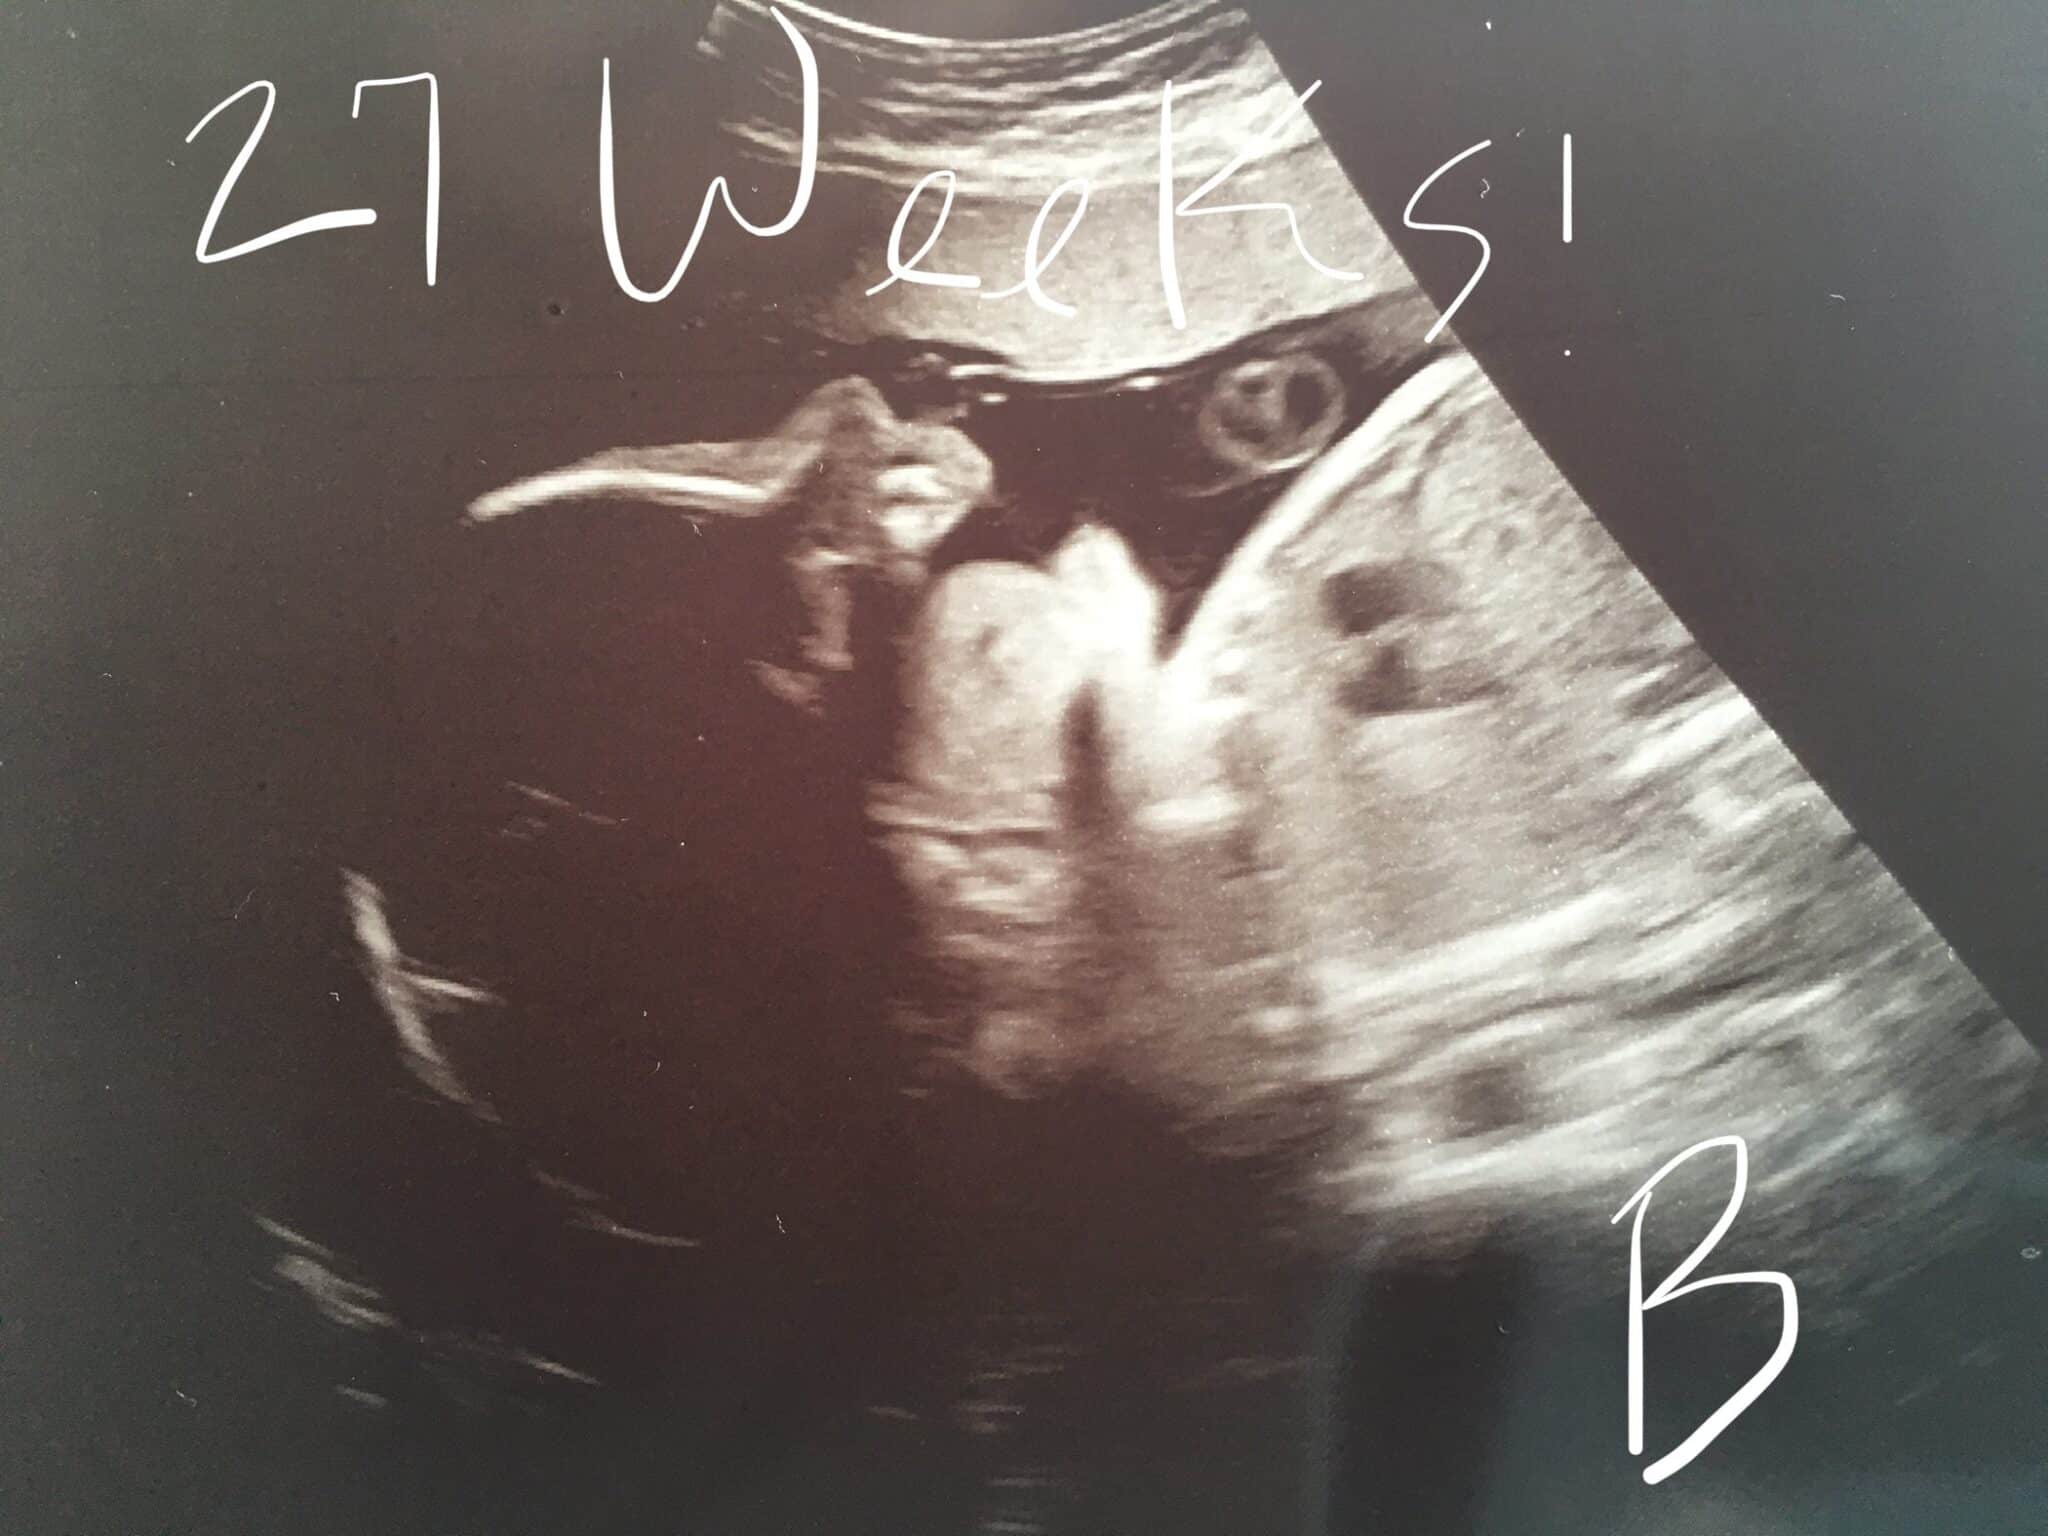

Ultrasound Photos at 27 Weeks Pregnant With Twins